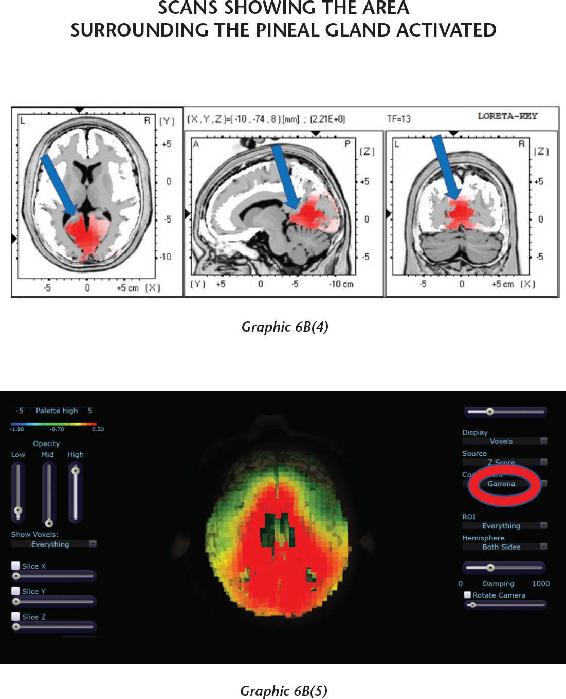

I also share two of my own personal stories here—experiences that have changed me at a very deep level. This book is as much about the mystical as it is about healing and creating new opportunities in our lives. I share these stories because I want to prime you for what is possible when we leave this realm of space-time (the Newtonian world we learned about in high school science class) and activate our pineal gland so we can move into the realm of time-space (the quantum world). Many of our students have had similar mystical and interdimensional experiences, which seemed as real as this material reality.

Once you are beyond your associations to this material world and you are in the unified field—chock-full of infinite possibilities—biological systems exist for taking that energy that’s beyond the vibration of matter and turning it into imagery in the brain. That’s where the pineal gland comes in, the subject of Chapter 12. Think of your pineal gland—a tiny gland perched in the central back area of your brain—as an antenna that can transduce frequencies and information and turn them into vivid imagery. When you activate your pineal gland, you are going to have a full-on sensory experience without your senses. That internal event will be more real to you in your mind while your eyes were closed than any past external experience you’ve ever had. In other words, in order to lose yourself fully in the inward experience, it has to be so real that you are there. When this happens, this little gland transmutes melatonin into some very powerful metabolites that cause you to have that type of experience. We will study the properties of this gland and then you will learn how to activate it.